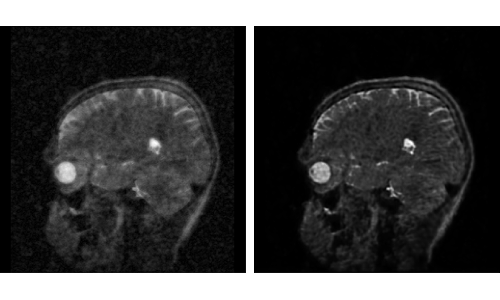

A supervised U-Net for MRI reconstruction from undersampled k-space data.